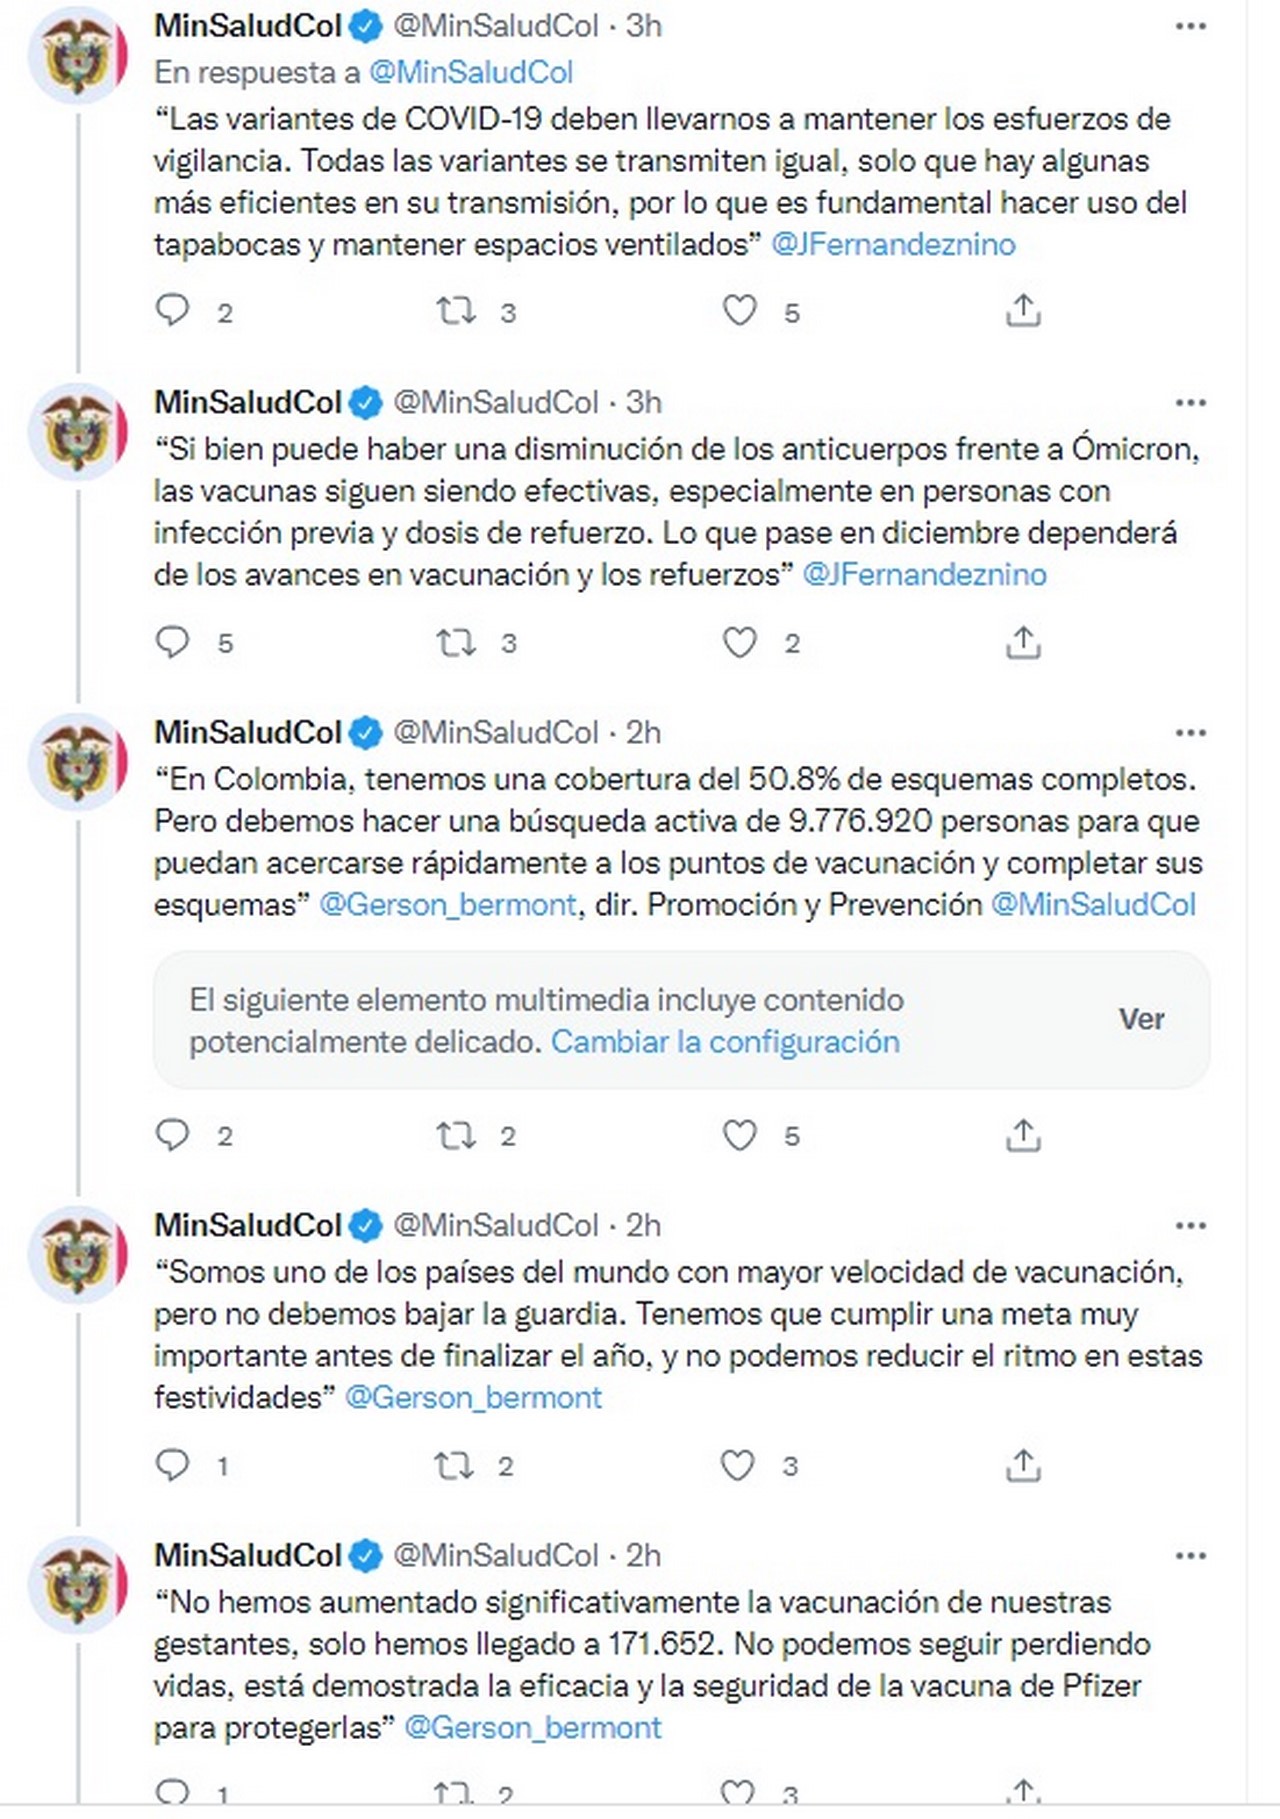

Por eso, en el marco del PMU número 113, liderado desde Cúcuta, Julián Fernández, director de Epidemiología y Demografía del Ministerio de Salud y Protección Social, aclaró algunas de las dudas sobre esta nueva variante y se refirió al eventual panorama de su llegada a Colombia.

De acuerdo con el funcionario, aún hay información que se desconoce sobre la cepa; sin embargo, ya hay algunas cosas claras. «Sabemos que es una variante con mayor trasmisibilidad y con eso me refiero a que es dos o hasta cuatro veces más veloz que Delta», dijo.

En segundo lugar, Fernández se refirió a la severidad de la variante Ómicron. Al respecto, indicó que aún hay debate sobre el tema. «No se sabe si es más, igual o menos severa. Pero no nos podemos relajar por eso. Más contagios representan más muertes, sobre todo en poblaciones no vacunadas», aseveró.

El epidemiólogo hizo énfasis en que las vacunas seguirían siendo efectivas contra Ómicron. «Es muy importante intensificar el trabajo. La diferencia de lo que pase en diciembre la hará la vacunación de personas de riesgo y los refuerzos con terceras dosis», agregó.

Sobre este mismo tema recordó que ya está demostrado que los refuerzos tienen mayor protección cuando son heterólogos, por eso alcaldes, gobernadores y personal de salud que atiende vacunación covid, deben estimular los refuerzos heterólogos en adultos de 50 años o más.

Finalmente, Fernández indicó que frente a la amenaza de nuevas variantes contagiosas el país debe fortalecer la vigilancia.